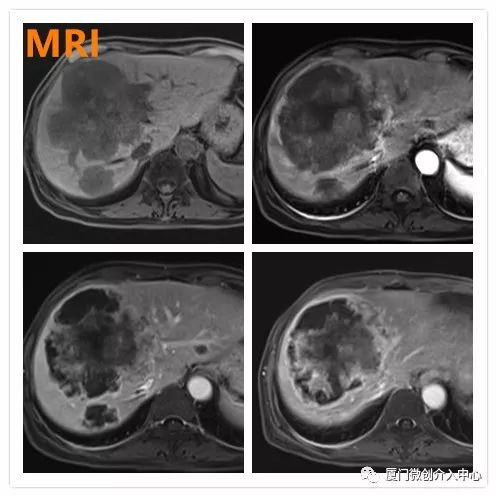

老年女性患者,诊断为乙状结肠腺癌并肝多发转移。肝脏肿瘤病灶巨大且多发,针对肝脏转移瘤行载药微球栓塞治疗,肠道肿瘤行动脉化疗灌注治疗。

肝动脉化疗栓塞+肠系膜上动脉化疗灌注治疗

术后1月复查提示肝转移瘤病灶内部明显坏死,肿瘤缩小

肠道肿瘤标志物明显降落(CEA 术前:3493 ng/mL,术后:196.3 ng/mL;CA19-9 术前:895.8 U/mL,术后:110.1 U/mL),病灶控制理想。